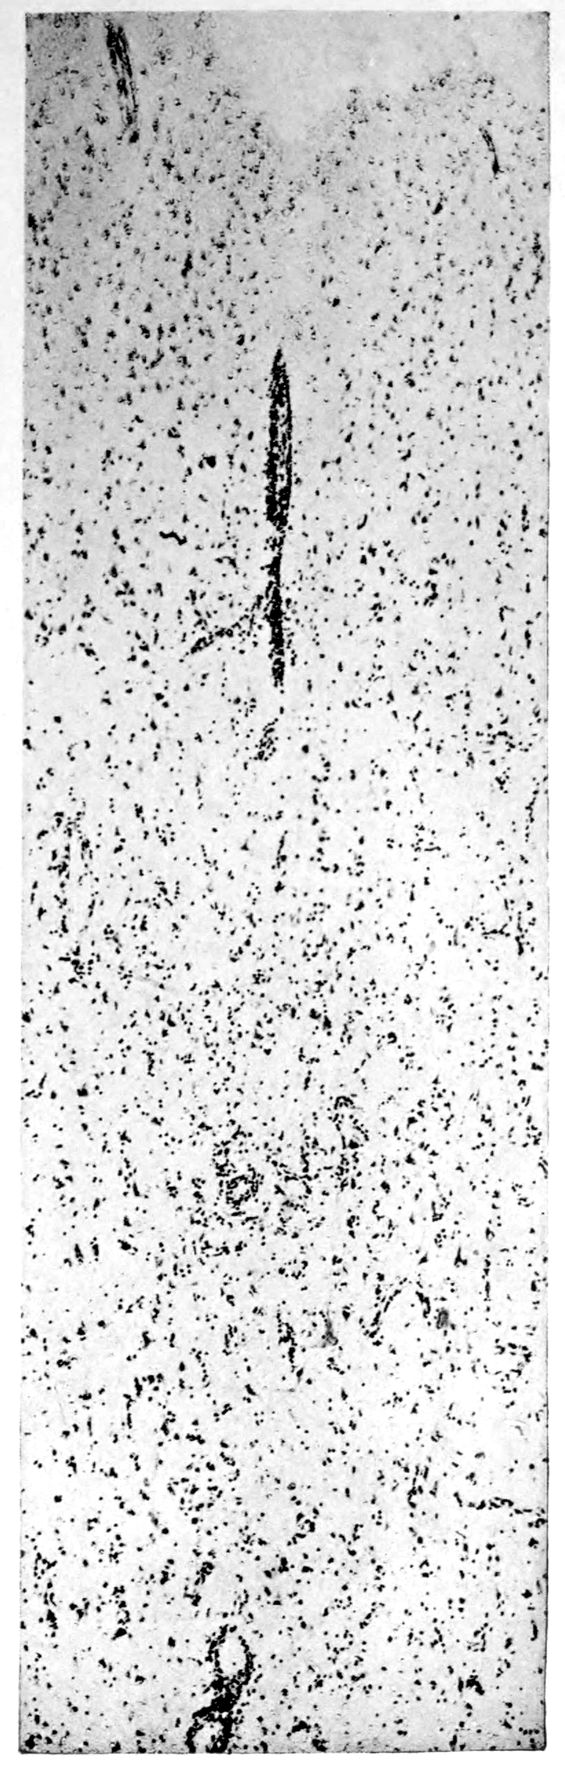

Apparent new formation of small blood vessel. Photographed by Dr. A. M. Barrett.

Rod cells (Stäbchenzellen) in paretic neurosyphilis. Photographed by Dr. A. M. Barrett.

Granular ependymitis—microscopic appearance of a marked example of “sanding” of ventricle.

41Characteristic and constant in paretic neurosyphilis is the Plasmocytosis and Lymphocytosis, Perivascular in distribution about small cortical vessels. There is also a characteristic (though characteristically less prominent) Plasmocytosis and Lymphocytosis, Meningeal in distribution. The pleocytosis of the spinal fluid, almost constant though variable in amount in life, is an indicator of the meningeal picture and less directly of the parenchymatous picture.

Granular Ependymitis (“sanding” of ventricle floors) is characteristic and may be regarded as part of the parenchymatous picture. This ependymitis is an indicator how chemical changes could be readily produced at least in the ventricular fluids, since the limiting membranes of the nerve tissue are here subject to multiple breaks. The “sanding” is a neuroglia reaction to these multiple small breaks (Weigert’s explanation).